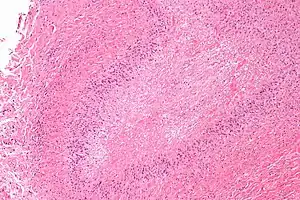

Micrograph of a rheumatoid nodule, showing the characteristic palisading granuloma with a core consisting of necrotic collagen and fibrin. H&E stain.

Histological examination of nodules shows that they consist of a shell of fibrous tissue surrounding a center of fibrinoid necrosis.[13] Pea-sized nodules have one centre. Larger nodules tend to be multilocular, with many separate shells or with connections between the necrotic centers. Individual necrotic centers may contain a cleft or several centers of necrosis may all open on to a large bursal pocket containing synovial fluid.

The boundary between the necrotic center and the outer fibrous shell is made up of the characteristic feature of the nodule, which is known as a cellular palisade. The palisade is a densely packed layer of macrophages and fibroblasts which tend to be arranged radially, like the seeds of a kiwifruit or fig.[13] Further out into the fibrous shell there is a zone that contains T cells and plasma cells in association with blood vessels.[14] The histology of pulmonary nodules are similar to that of subcutaneous nodules, with central necrosis surrounded by palisading macrophages and inflammatory infiltrate.[5]